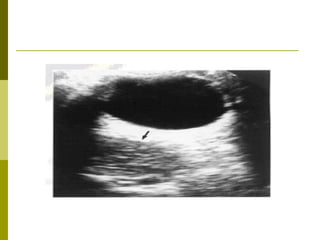

Posterior scleral thickening on B-ultrasound scan

Posterior scleral thickeningon B-ultrasound scan